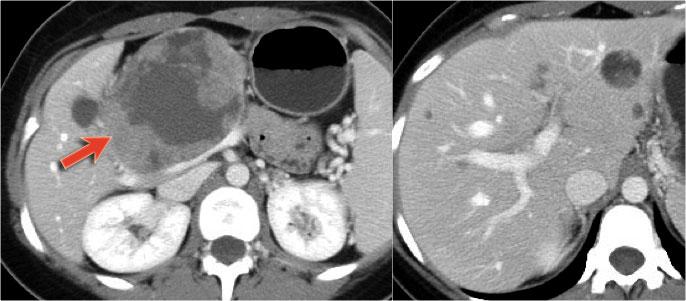

Hình ảnh CT của bệnh nhân nữ 51 tuổi có tiền sử sỏi mật và đau bụng.

Ghi nhận tổn thương giảm tỷ trọng với vôi hóa trung tâm ở đầu tụy.

Tổn thương có bờ viền thùy múi.

Tiếp tục xem hình ảnh MRI.

MRI thể hiện rõ hơn các đặc điểm hình thái của tổn thương (hình).

Trên chuỗi xung T2W, tổn thương có dạng đa nang.

Lưu ý vùng giảm tín hiệu trung tâm do sẹo trung tâm kèm vôi hóa.

Mặc dù một số nang có kích thước khá lớn, đây vẫn là hình ảnh đặc trưng của u nang tuyến thanh dịch (dạng đại nang).